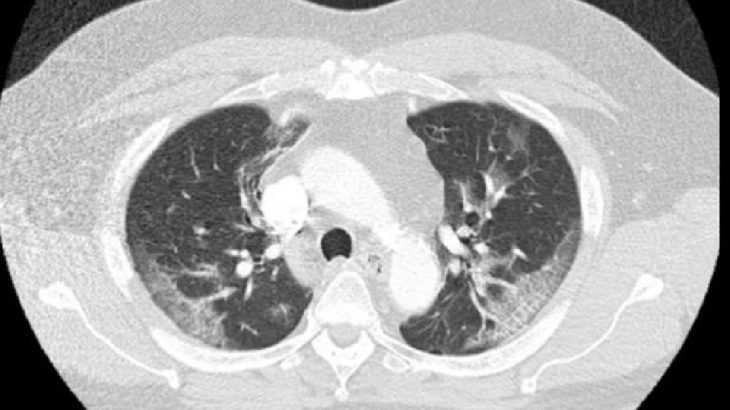

Chicago’da yaşayan hastanın 37.3 derece ateş ve hıçkırığı haricinde gözle görülür bir semptomu yoktu. Fakat yapılan tahlilde adamın ciğerlerinin kapasitesinin düşük olduğu ortaya çıktı.

Makalede, 62 yaşındaki Chicagolu bir adamın dört gün boyunca hıçkırdığı ve bunun aralıksız devam ettiği kaydedilirken, “Hiç semptom göstermiyordu ve ateşi ölçüldüğünde de 37.3 derece ateşi vardı. Fakat hastaneye kaldırılıp testler derinleşince durum ortaya çıktı. Corona virüsü testi pozitif çıktı ve ciğerlerinin kapasitesinin de düştüğü görüldü. Adamın ateşi de daha sonra 38.4’e çıktı” ifadesi kullanıldı.